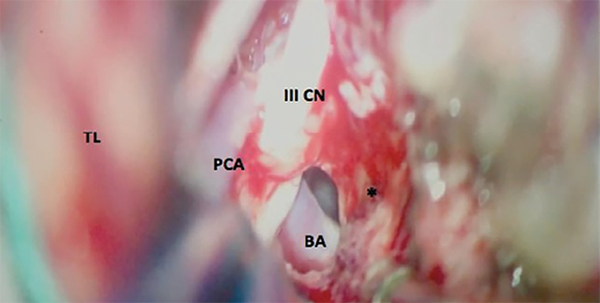

Uno de los abordajes más versátiles para la extirpación de meningiomas petroclivales que no se extienden hacia la fosa media es el abordaje retrosigmoideo (Figuras 6 y 7). El abordaje retrosigmoideo es más simple y fácil de realizar en comparación con los abordajes mencionados anteriormente. Está indicado cuando el tumor se encuentra principalmente en la fosa posterior, con una pequeña extensión en la fosa media y la porción posterior del seno cavernoso. En decúbito lateral o dorsal con rotación y extensión lateral de la cabeza, la incisión de la piel comienza en la región retromastoidea, 5 centímetros detrás del conducto auditivo externo, y se extiende 2 centímetros desde la punta de la mastoides, terminando en la parte superior del cuello. La fascia y los músculos se cortan hacia abajo, exponiendo el hueso occipital, el asterion y la región retromastoidea. Se realiza una craneotomía de cuatro centímetros de diámetro exponiendo los senos transverso y sigmoideo. La vena emisaria del mastoideo se coagula y se corta. Se hace una incisión en la duramadre paralelamente al seno sigmoideo, retrayendo ligeramente el aspecto lateral del cerebelo. El primer paso después de abrir la duramadre es drenar el líquido cefalorraquídeo de la cisterna cerebelomedular. Los pares craneales VII y VIII generalmente se encuentran posteriores a la cápsula tumoral, a menudo se incorporan al tumor, y se debe realizar una disección muy cuidadosa con monitoreo neurofisiológico intraoperatorio. El V par craneal se encuentra en el polo superior del tumor o se desplaza hacia arriba con el IV par craneal a través del margen libre del tentorio. El VI par craneal generalmente se encuentra en la parte anterior y en la superficie medial del tumor. Su identificación y disección solo es posible después de una extensa reducción de la lesión. Después de la coagulación de los accesorios durales, se realiza una resección intracapsular fragmentada entre los nervios craneales, a través de "ventanas" (tentorio-V; V-VII y VIII; VII y VIII-IX, X, XI). El envolvimiento tumoral de la arteria basilar y sus ramas, así como la arteria vertebral, es común en los exámenes preoperatorios. Sin embargo, generalmente hay un buen plan de disección durante la cirugía (Figura 5). La disección del plano aracnoideo alrededor de los vasos y nervios craneales es necesaria para preservar estas estructuras. El abordaje retrosigmoideo permite la resección del tumor desde el foramen yugular hasta la parte posterior del seno cavernoso. El tumor con extensión a la fosa media puede resecarse, abriendo el tentorio y drenando el tubérculo suprameatal y el ápex petroso14. Después de la extirpación total del tumor, se debe realizar un cierre preciso de la duramadre. Todas las celdas mastoideas abiertas son selladas con injerto muscular y pegamento de fibrina. Algunos modelos fueron desarrollados para tratar de medir varios elementos de la resecabilidad de los meningiomas petroclivales. Entre ellos, Abdel-Aziz et al desarrollaron un mecanismo para predecir la reexpansión posquirúrgica del tronco encefálico después de los abordajes petrosos anteriores o posteriores. Se propuso una nueva escala de clasificación basada en el tamaño de la resección y la calidad de la descompresión del tronco encefálico. Para Siwanuwatn et al el abordaje transcoclear es el que proporciona el espacio más amplio para el acceso petroclival; sin embargo, se debe sacrificar la audición.15 Todos estos abordajes son complejos y con un gran potencial de complicaciones si no hay un conocimiento claro de la anatomía. Los autores sugieren capacitación en un laboratorio de microcirugía y anatomía antes de llevar a cabo estos abordajes.

Figura 5: Imagen intraoperatoria de la Figura 2. Después de la resección del meningioma petroclival, se visualiza el nervio oculomotor (III CN). Arteria basilar (BA) y arteria cerebral posterior (PCA). El lóbulo temporal (TL) está ligeramente retraído. El sitio de implantación del tumor está representado por *